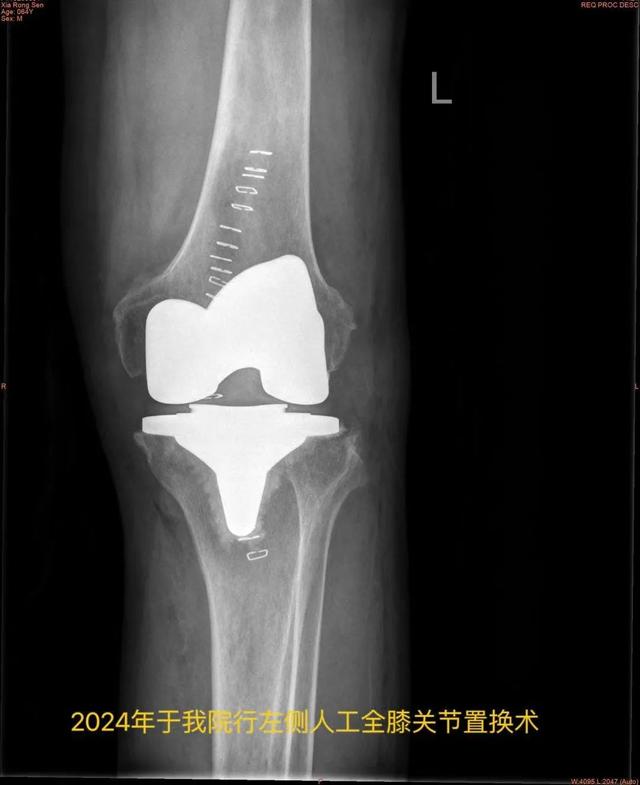

今年64岁的王大爷(化姓),双侧髋、膝关节疼痛十余年,六年前因“腰腿疼痛”于上海长征医院行腰后路减压植骨融合内固定术,同年于上海新华医院内分泌/遗传科行基因检测诊断为“黑尿病”,四年前因“左髋疼痛”于我院行“左侧人工全髋关节置换术”,一年前因“右膝疼痛”于我院行“右侧人工全膝关节置换术”。

近日,王大爷因“左膝关节步行活动后疼痛加剧”门诊拟“黑尿病性膝关节炎”再次入住我院骨科,入院后查体:全身皮肤出现黑色素沉着,以面部及耳廓皮肤黑色斑块沉着明显,左膝关节周围肿胀,有压痛,左膝关节屈曲100°,伸直约10°(正常膝关节活动度为屈曲135°,伸直0°)。

现患者术后第三天

可下地行走进行康复训练

复查示左膝关节假体位置良好